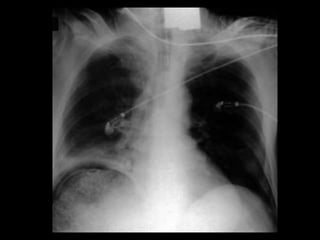

Alterações Pulmonares 20

Pleuropulmonares + +++